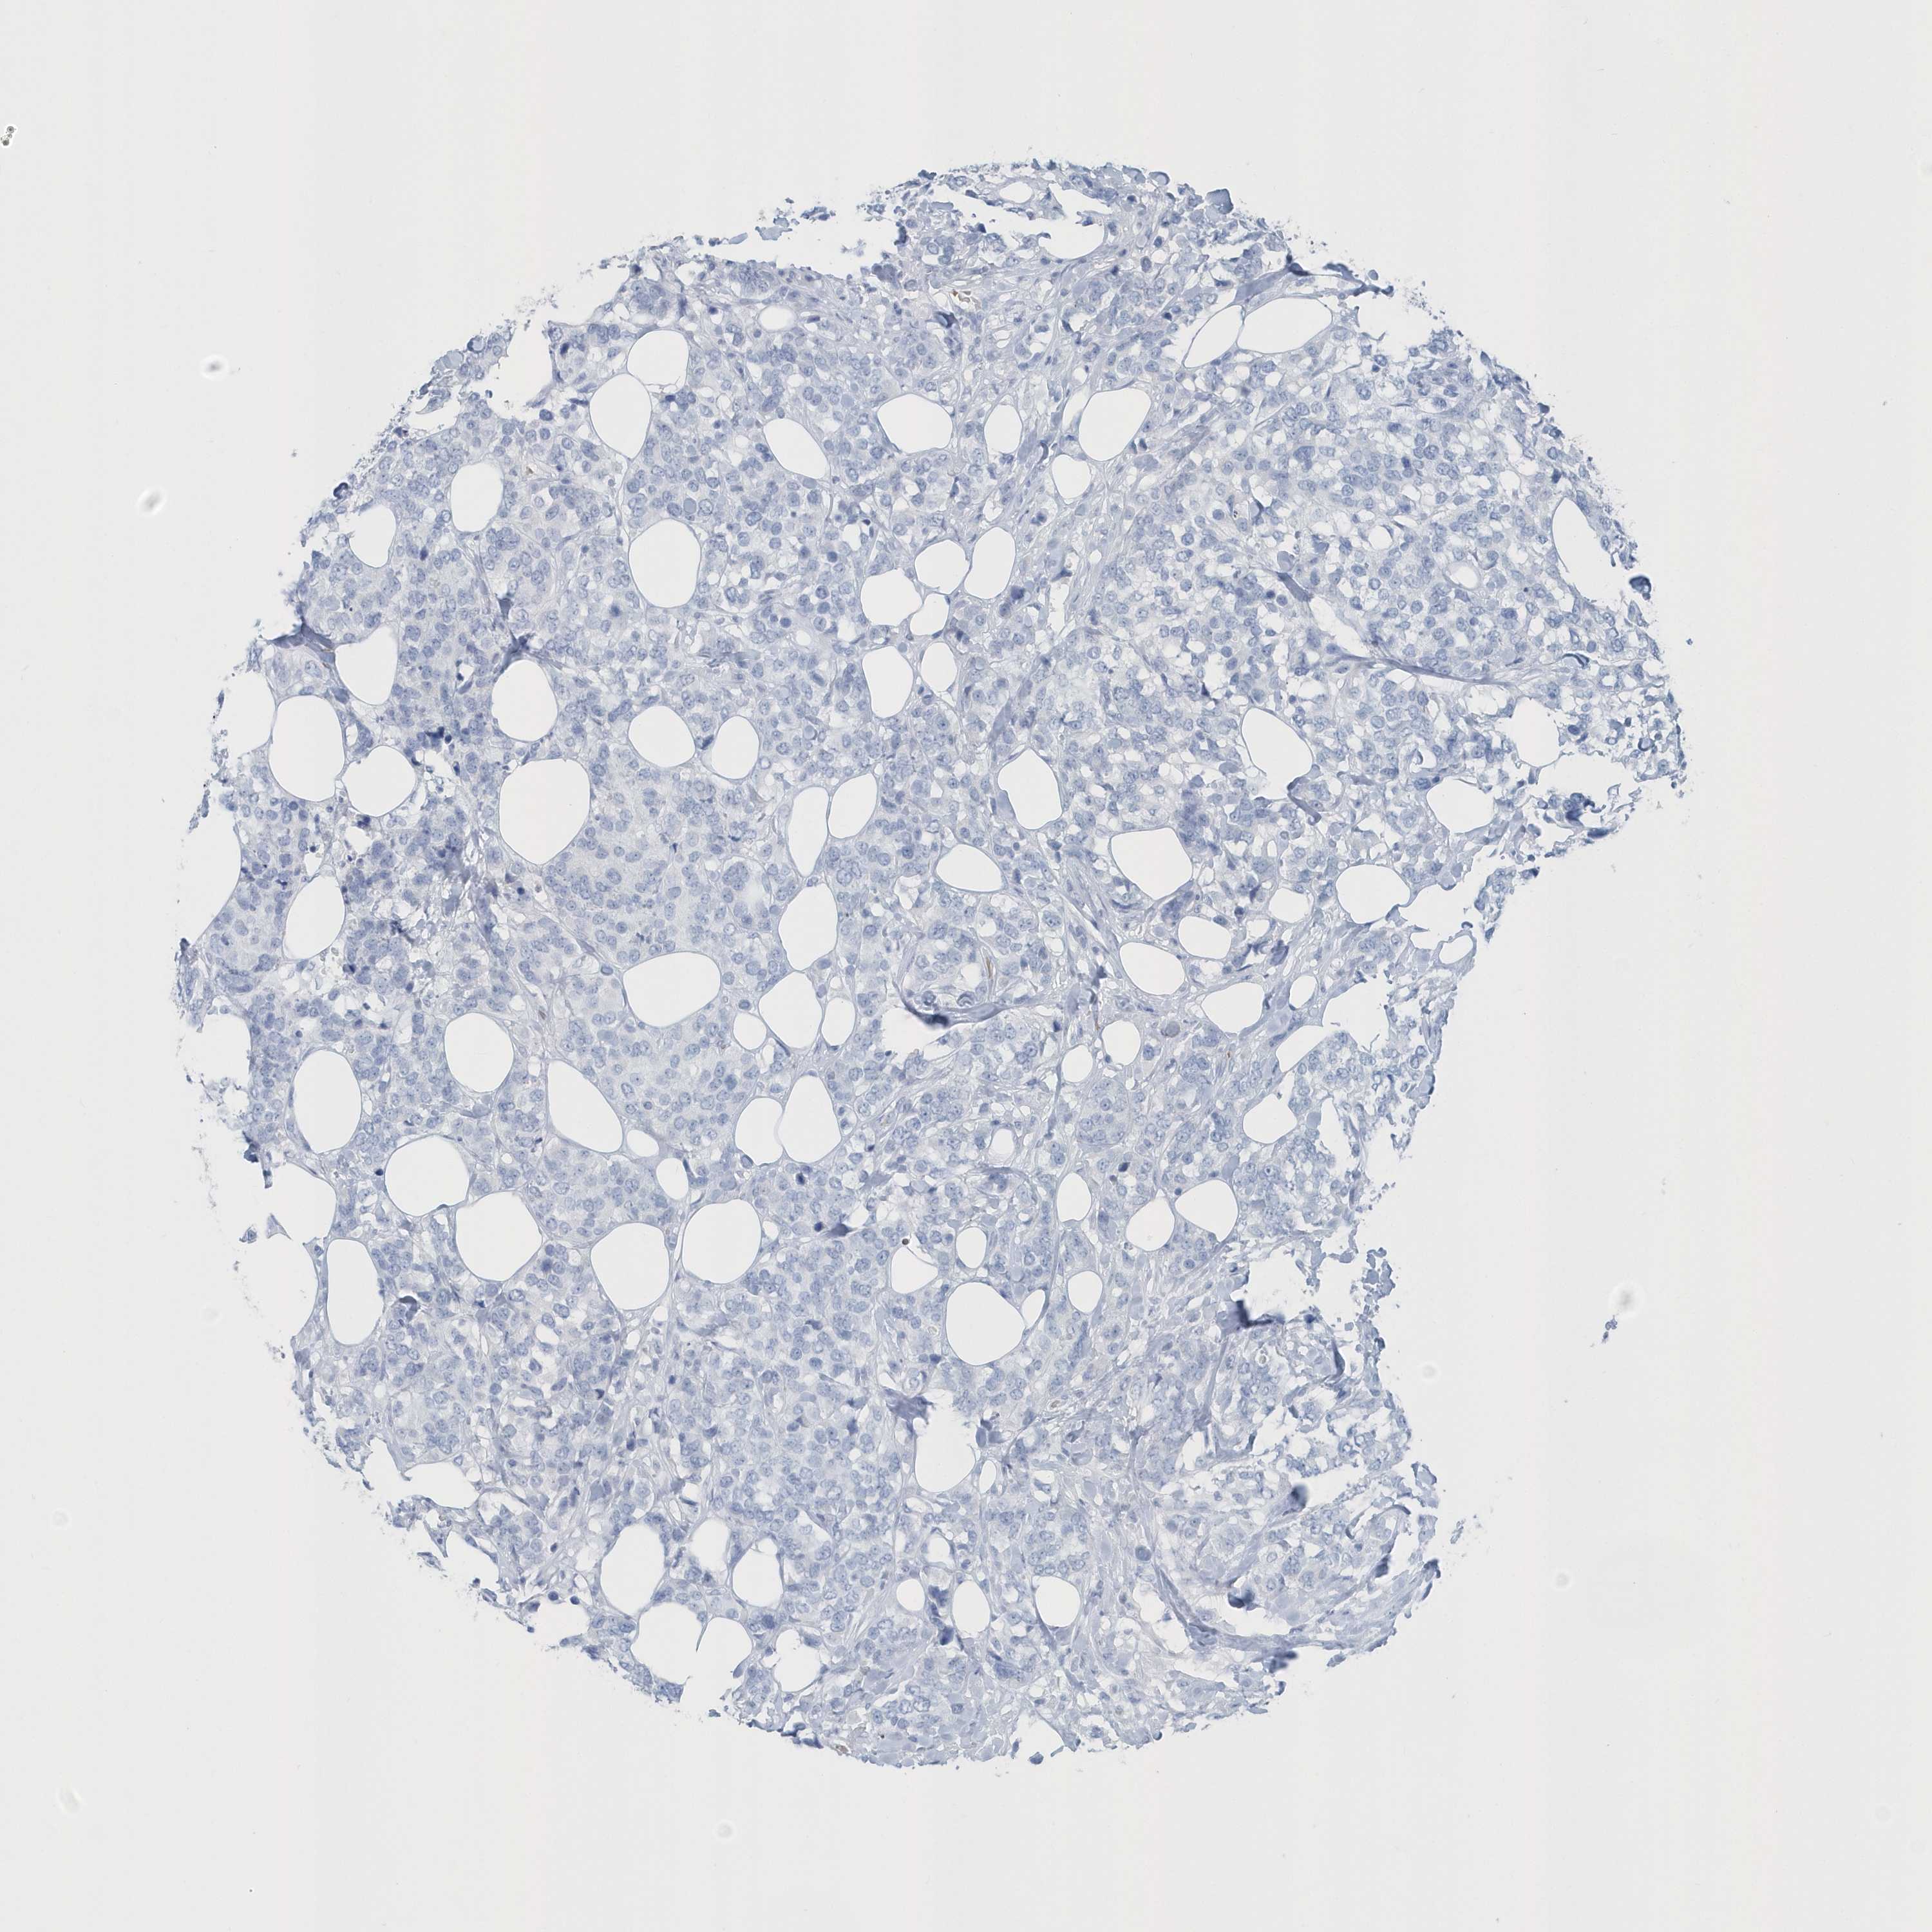

Breast cancer

Human cancer